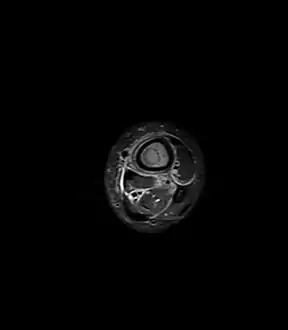

Fat saturated STIR (short tau inversion recovery) image showing hyperintense edema in the calf musculature, marrow edema, and subperiosteal pus. The intramedullary abscess cavity is hyperintense as well.